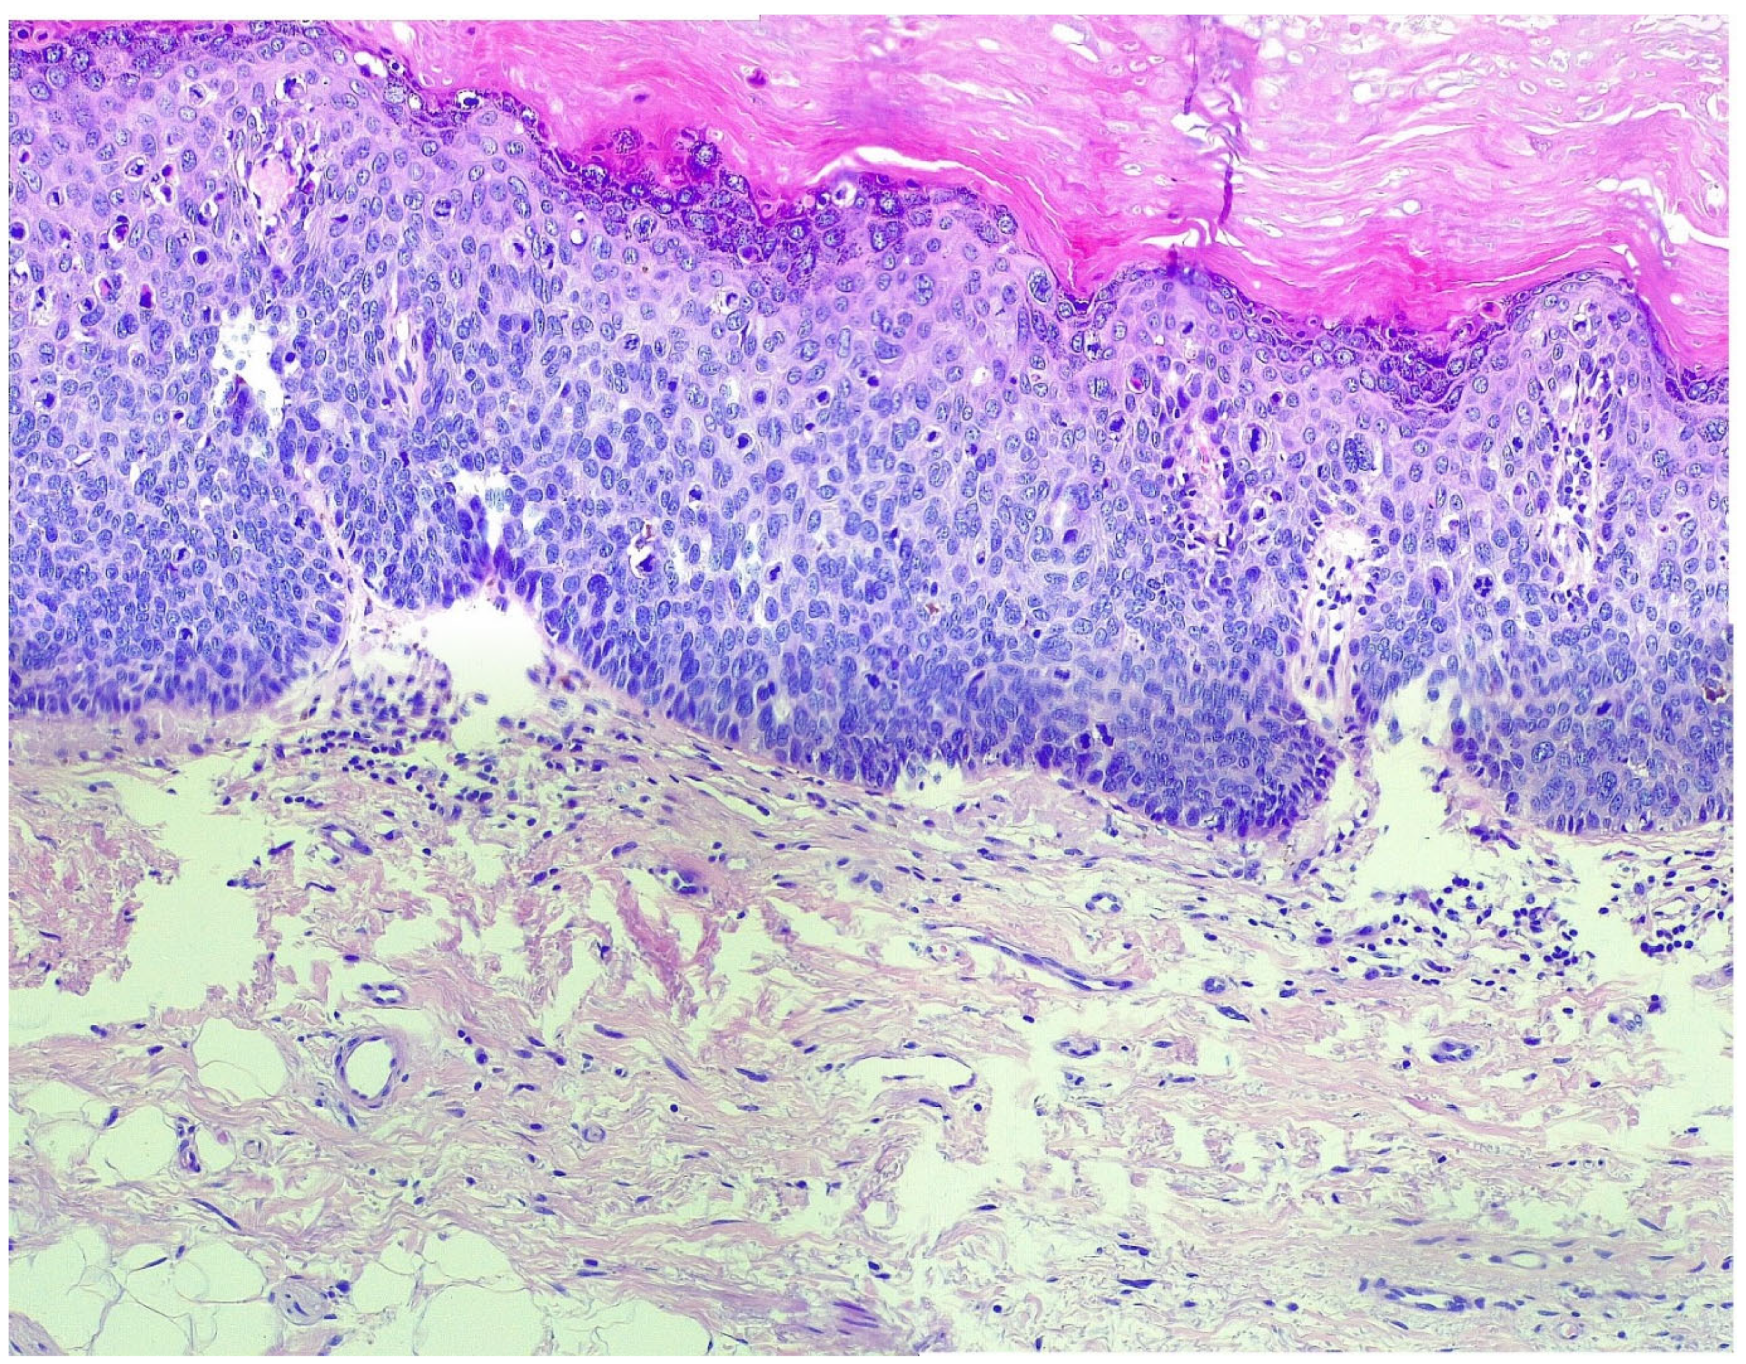

The Clinical Management and Outcomes of Two Cases of Vulvar Neoplasms: A Two-Case Study of VIN 3 and Stage IA Vulvar Keratinizing Squamous Cell Carcinoma

2.1. Patient A